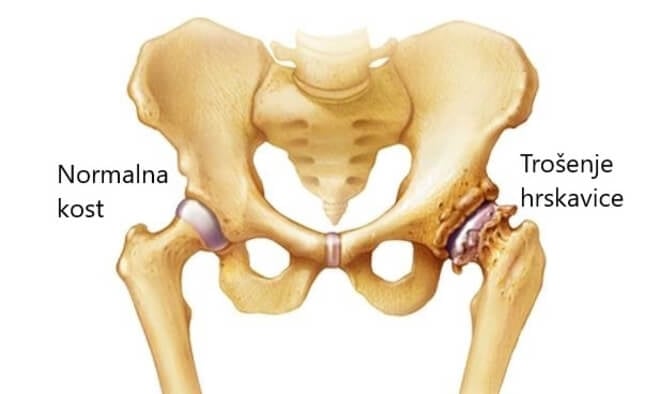

Ovaj lijek protiv bolova preporučuje se za liječenje boli i osjetljivosti najčešćeg tipa artritisa a to su vam osteoartritisa koljena, šaka i drugih zglobova. Teuflex gel za ublažavanje bol u zglobovima također se može koristiti za ublažavanje bolova u zglobovima zbog reumatoidnog artritisa ili za ublažavanje bolova u mišićima i manjih bolova u leđima.